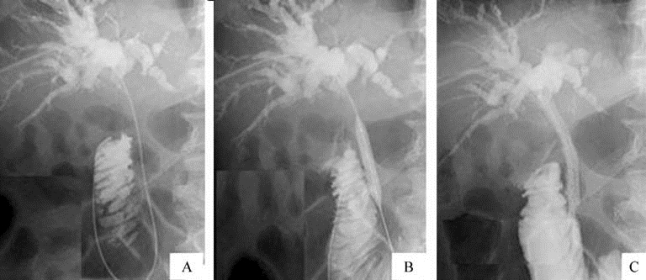

图21-32 经皮肝穿刺胆管引流(PTCD)

A.导丝通过胆管闭塞段;B.球囊扩张;C.置入内引流涵管